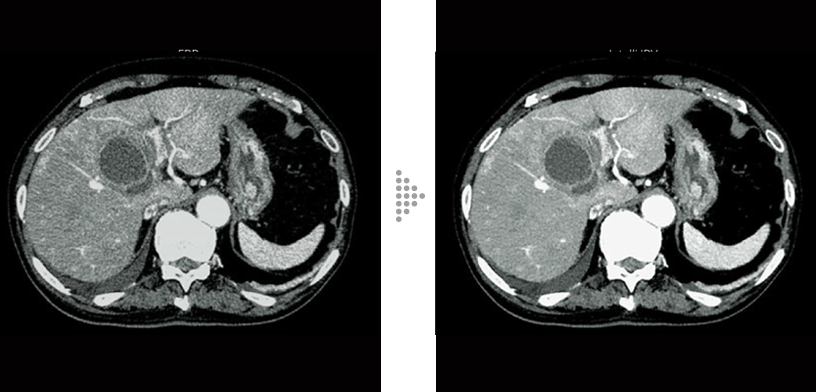

FBP(izquierda)

Intelli IPV(derecha)